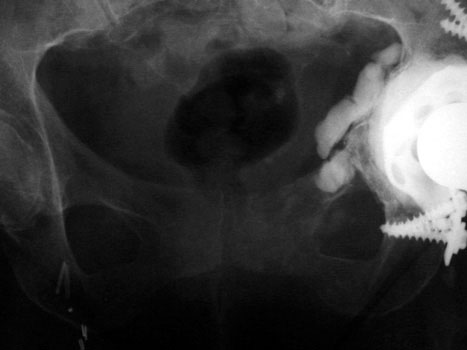

FRACTURES

STRESS OR INSUFFICIENCY

Left pubic bone

Left inferior pubic ramus